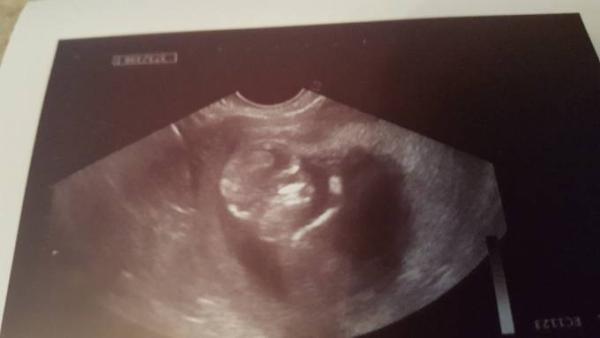

Hallo ihr Lieben. Ich hatte nach der langen Wartezeit heute endlich meinen Termin. Es ist alles super. Der Krümel ist jetzt 5,3cm groß und hat mir fleißig zu gewunken.

Ich bin so verliebt und glücklich.